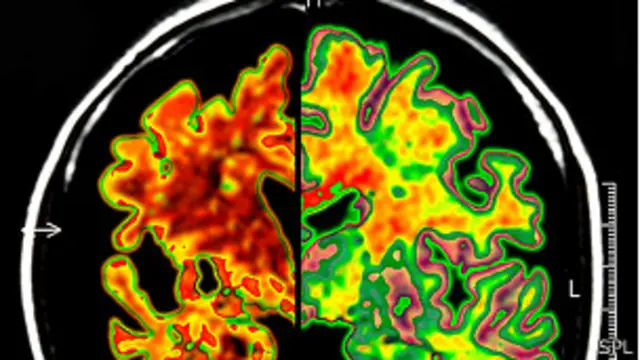

توضحت لدى العلماء صورة لأسباب مرض الزهايمر بعد إجراء أكبر تحليل للحمض النووي (دي أن أيه) للمرضى المصابين به.

بيد أن الاسئلة الأساسية عن أسباب الخرف، وكيفية موت خلايا الدماغ، فضلا عن كيفية معالجتها أو حتى تشخيصها ما زالت بلا إجابة واضحة.